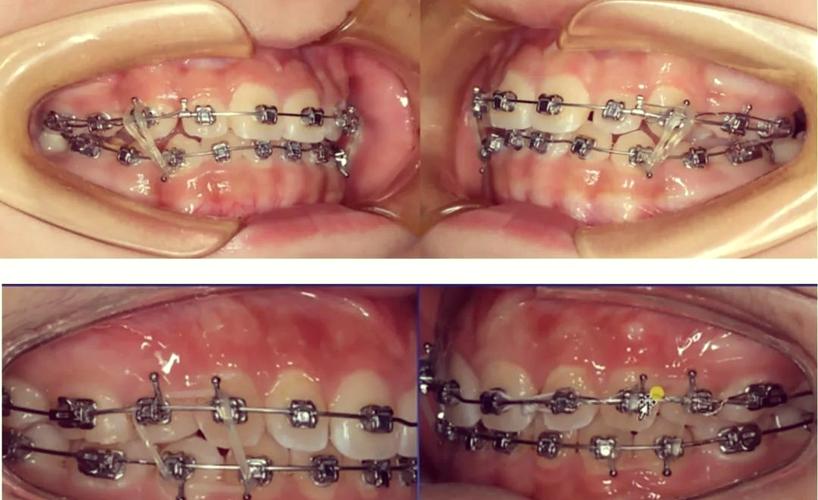

适用于牙性或轻度功能性前牙开合,通过压低上前牙、伸长下前牙改善覆颌,常用装置为“多用途弓(MEAW)+垂直牵引钩”,在上颌弓丝的侧切牙与尖牙间焊接垂直牵引钩,下颌弓丝末端弯制停止曲,使用橡皮圈连接上下颌牵引钩,施加垂直向牵引力,牵引力一般控制在50-70g,每天更换橡皮圈,避免力量衰减,该方法需注意控制牵引角度,避免上前牙过度唇倾或下前牙牙根吸收。 -

后牙颌间牵引

对于功能性或轻度骨性开合,尤其是伴随下颌后牙伸长者,可通过后牙颌间牵引抑制后牙垂直向生长,同时利用“楔形效应”引导下颌向前旋转,改善前牙开合,具体操作为在上颌第一磨牙制作带环并焊接牵引钩,下颌第一磨牙舌侧焊接牵引钩,使用Ⅲ类或Ⅱ类牵引橡皮圈(根据开合类型调整方向),每天佩戴20-22小时,牵引期间需密切观察后牙移动情况,避免后牙过度伸长加重开合。

(图片来源网络,侵删) -